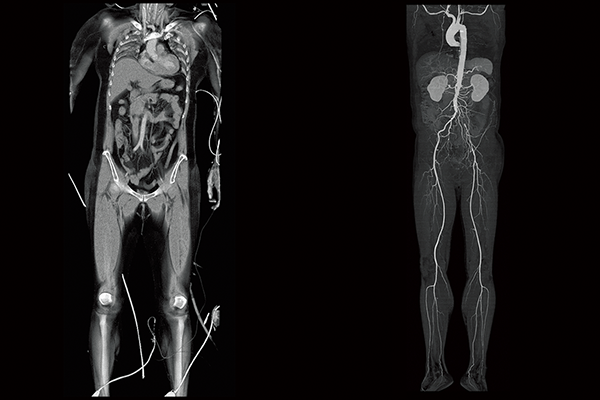

Abdominal aortic occlusion

Intraoperative oxygen desaturation(Left)

Left common iliac artery occlusion(Right)